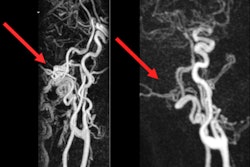

The German Roentgen Society (DRG), the German Society for Neuroradiology (DGNR), and the German Society for Interventional Radiology and Minimally Invasive Therapy (DeGIR) are promoting their collective range of additional qualifications that provide specialist knowledge and practical experience in the diagnosis of heart, prostate, muscle, and joint diseases as well as in the minimally invasive therapy of vascular diseases, cancer, strokes, and neurovascular diseases.